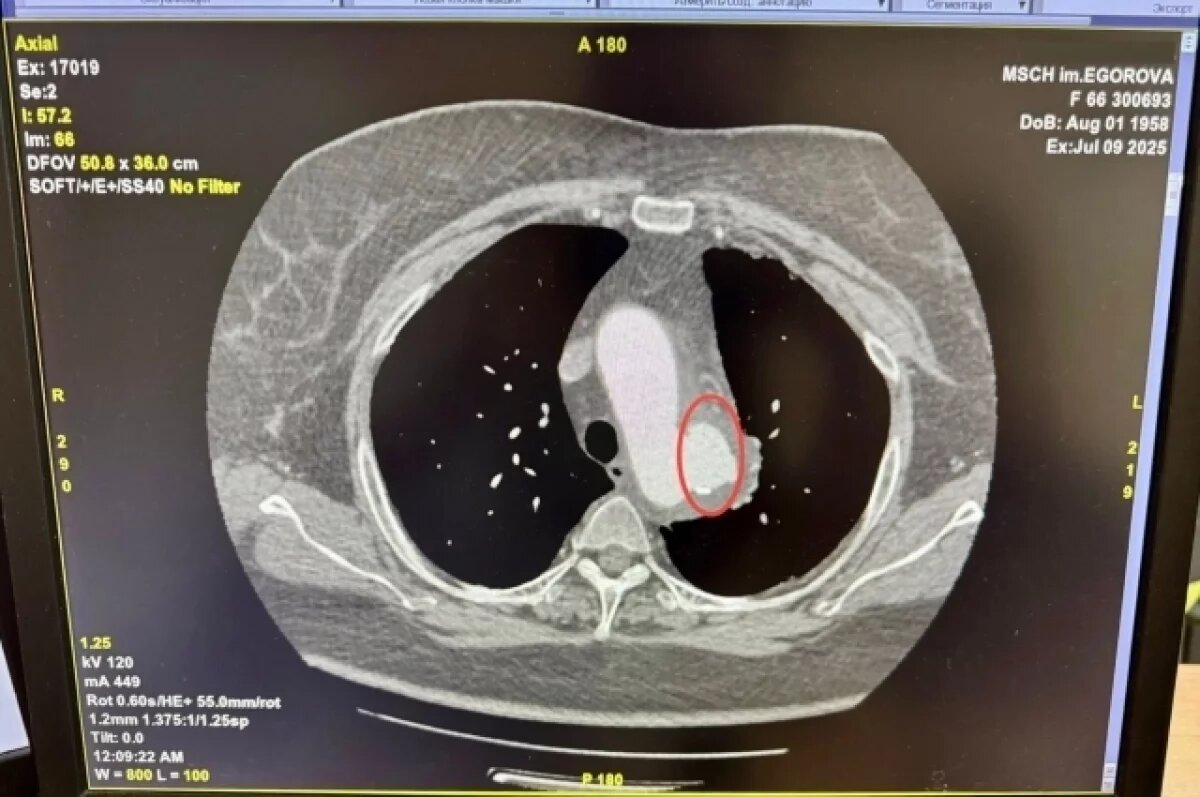

В экстренном порядке, глубокой ночью, вместе с заведующей рентгенологическим отделением Ларисой Теряговой было принято решение о проведении КТ-ангиографии грудного отдела аорты. Исследование подтвердило тяжёлый диагноз: на полученных изображениях чётко просматривалась аневризма (истончение стенки) нисходящего отдела грудной части аорты.

Фото: Министерство здравоохранения Ульяновской области